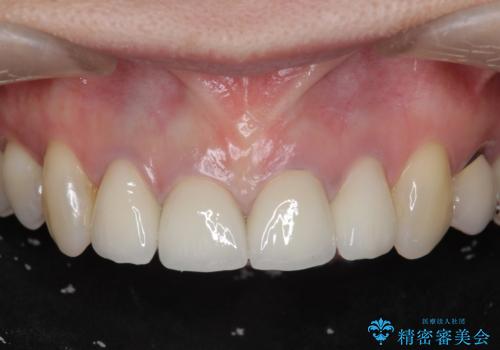

金属色の目立つ前装冠を除去し、発生していた小さな虫歯を丁寧に全て除去しジルコニアセラミッククラウンで審美的な前歯となるような治療を計画します。

金属を用いないジルコニアセラミッククラウンは透明感の再現性に優れ、審美性と自然な仕上がりの両立を期待することができます。